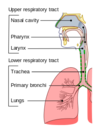

What are the two parts of the respiratory tract?

Upper and lower respiratory tract

What structures make up the upper and lower respiratory tract?

Upper = Nasal cavity – > larynx

Lower = Trachea –> alveoli

Label the diagram